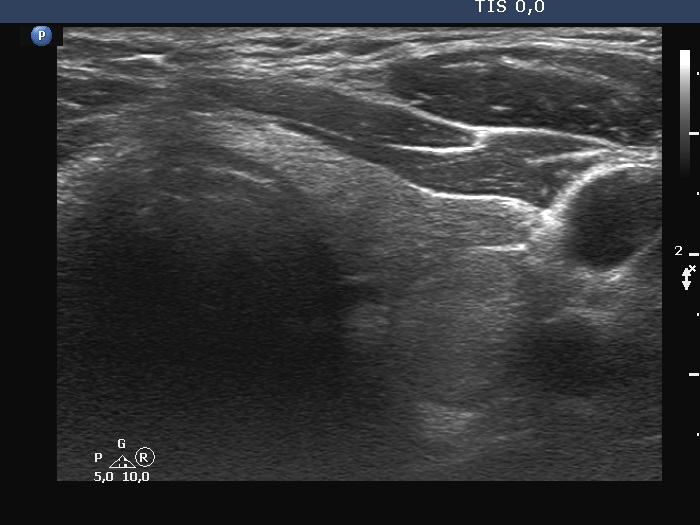

Examination a year after the first visit (third row of images):

Clinical presentation: The patient had no complaints.

Palpation: no abnormality.

Laboratory tests: TSH 1.60 mIU/L, FT4 15.6 pM/L, aTPO 12 U/mL.

Ultrasonography: The dorsal part of the right lobe remained hypoechoic. The nodule in the left lobe has increased in size and presented halo and signs of perinodular vascularity.

Cytology of the nodule resulted in benign lesion.

Suggestion: repeat examination in three years.

Comment. In the active phase of subacute thyroiditis, a nodule can be obscured. The real structure of the thyroid can be revealed only when the hypoechogenicity disappears or decreases significantly.